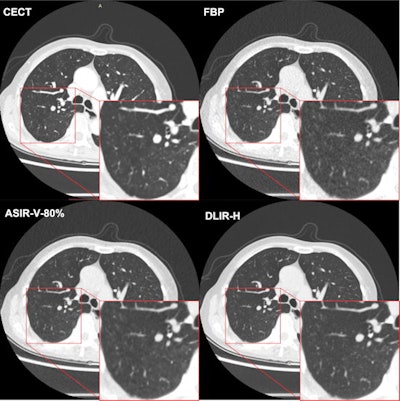

A team of researchers led by Beibei Jiang of Shanghai Jiao Tong University School of Medicine prospectively assessed three different image reconstruction techniques for their image quality and ability to detect lung nodules on ultralow-dose CT exams. The group found that deep learning-based reconstruction outperformed filtered back projection (FBP) and adaptive statistical iterative reconstruction (ASIR-V) for both metrics.

"Compared with adaptive statistical iterative reconstruction-V, deep learning image reconstruction ... improved the image quality by reducing image noise and increasing the lung nodule detection rate," the authors wrote. "[Deep learning image reconstruction] also improved the nodule measurement accuracy and displayed more detailed malignancy-related imaging features of nodules."

To determine if deep learning-based image reconstruction could help, the authors prospectively studied 203 consecutive patients at Shanghai General Hospital from April to June 2020 who had received noncontrast ultralow-dose CT performed at 0.07 or 0.14 millisieverts -- similar to the level of a single chest radiograph -- as well as a contrast-enhanced CT exam. All ultralow-dose CT images were reconstructed with filtered back projection, ASIR-V, and a commercial deep learning-based image reconstruction algorithm (TruFidelity, GE Healthcare).